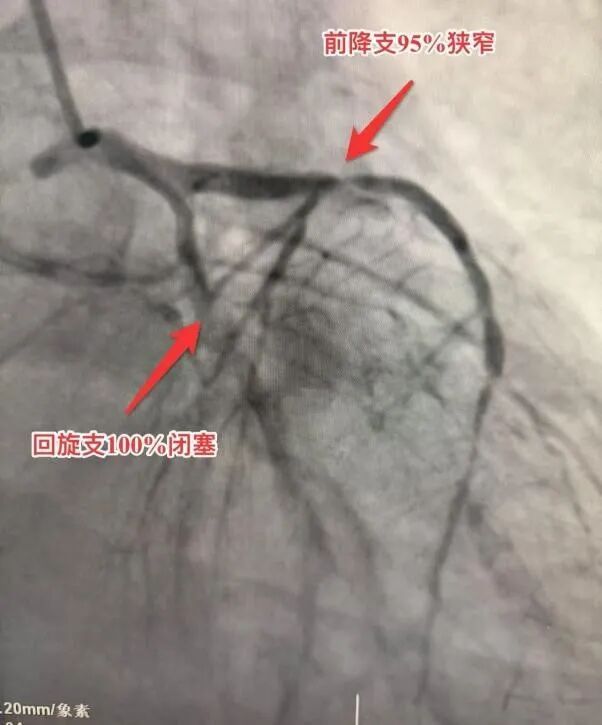

死里逃生后的康先生终于接受了冠脉造影检查。结果令人震惊:实际冠脉病变程度比CTA显示的还要严重。前降支近段95%狭窄,而回旋近段和右冠中段更是完全闭塞,如同两颗沉默的炸弹。

面对远超预期的结果,冠脉介入专家小组结合病情及心电图,审慎评估,由马江伟主任主导,为患者在前降支及左回旋支精准植入两枚支架。术后造影显示,血流恢复至理想的TIMI 3级,血运重建成功。